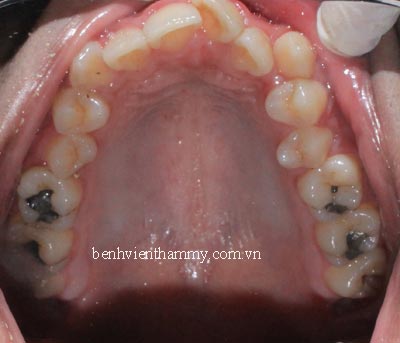

(Hình ảnh sau thời gian điều trị 16 tháng)